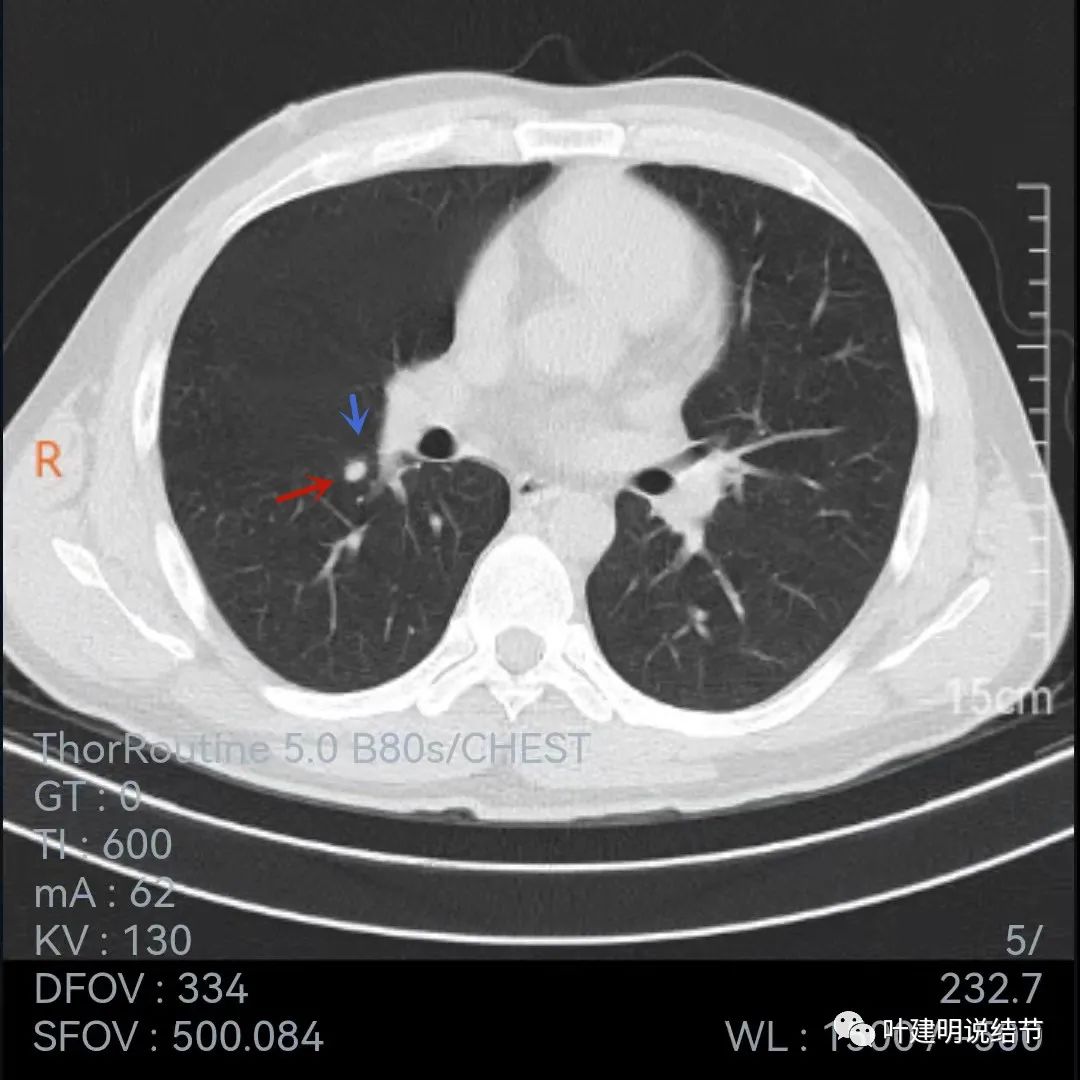

我们再来看2019年的片子:

上面是2019年5月份的片子,不是薄层,只有这两个层面见到病灶,是实性小结节,叶间裂似略有牵拉,病灶边缘比较光滑,密度相对较均匀,没有毛刺或血管征,单看应该良性结节可能性大,至少先随访。